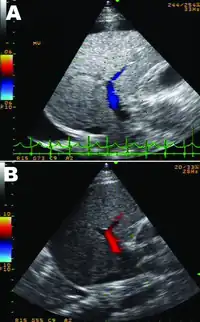

| A person with massive ascites and caput medusae due to cirrhotic liver failure | |